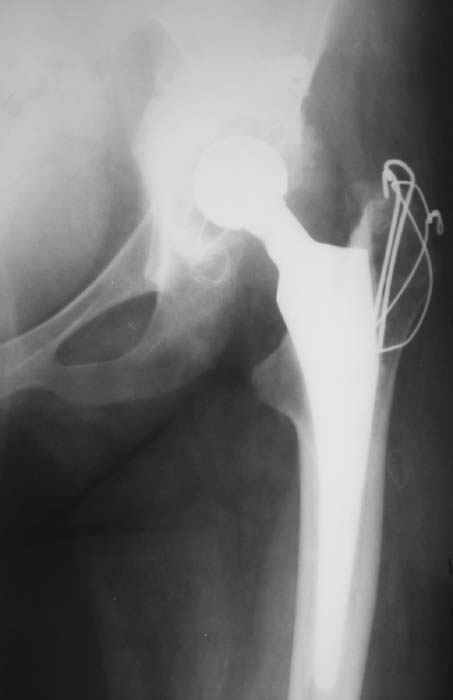

Уважаемые коллеги! Женщина, 28 лет. Страдает ревматоидным полиартритом, гормонозависима. 6 месяцев назад перенесла тотальное эндопротезирование левого тазобедренного сустава по поводу протрузионного коксита.

Использована цементная версия с пластикой дна впадины измельченной аутокостью и гранулами гидроксиапатита. Субъективное улучшение после операции. Улучшилось и стабилизировалось общее состояние. В настоящее время затруднено передвижение из-за поражения правого коленного сустава. Болезненный и <болтающийся> сустав. Предполагается замена сустава протезом без сохранения задней крестообразной связки. Возможные варианты? Заранее благодарю! С уважением, А.В.Владзимирский Донецкий НИИ травматологии и ортопедии Донецк, Украина